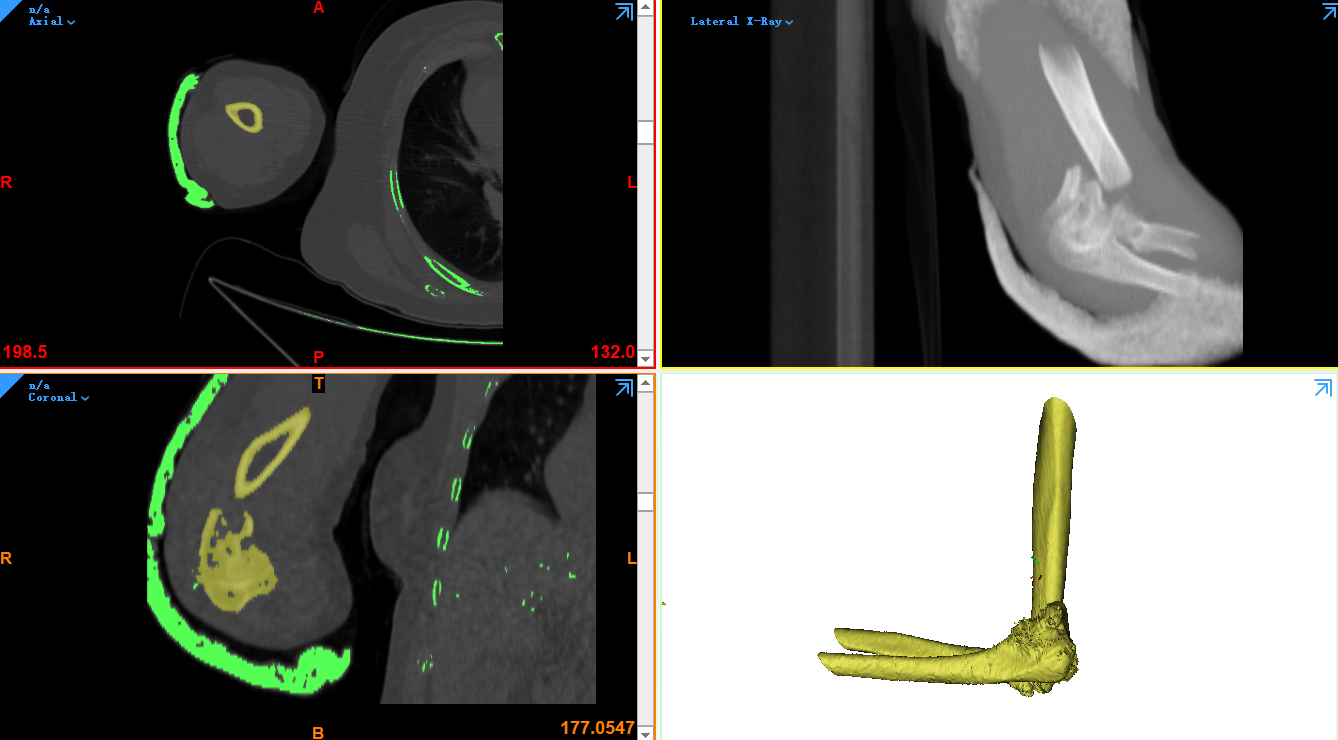

另外的醫(yī)療領(lǐng)域三維掃描技術(shù)同樣起到不可代替的作用。例如根據(jù)CT斷面圖像,構(gòu)建人體骨骼模型的方案,就離不開三維掃描技術(shù)的支持。根據(jù)CT獲取的三維模型不僅可以直觀的觀察病人的病情,還能夠制作手術(shù)導(dǎo)板,將再次降低醫(yī)療手術(shù)的風險。除此之外先前一段時間被炒得火熱的胎兒打印話題,則是根據(jù)三維彩超數(shù)據(jù)斷面數(shù)據(jù)創(chuàng)建的胎兒模型,而后或進行3D打印或進行水晶內(nèi)雕生成胎兒模型的三維掃描技術(shù)。

正在根據(jù)CT數(shù)據(jù)創(chuàng)建三維模型